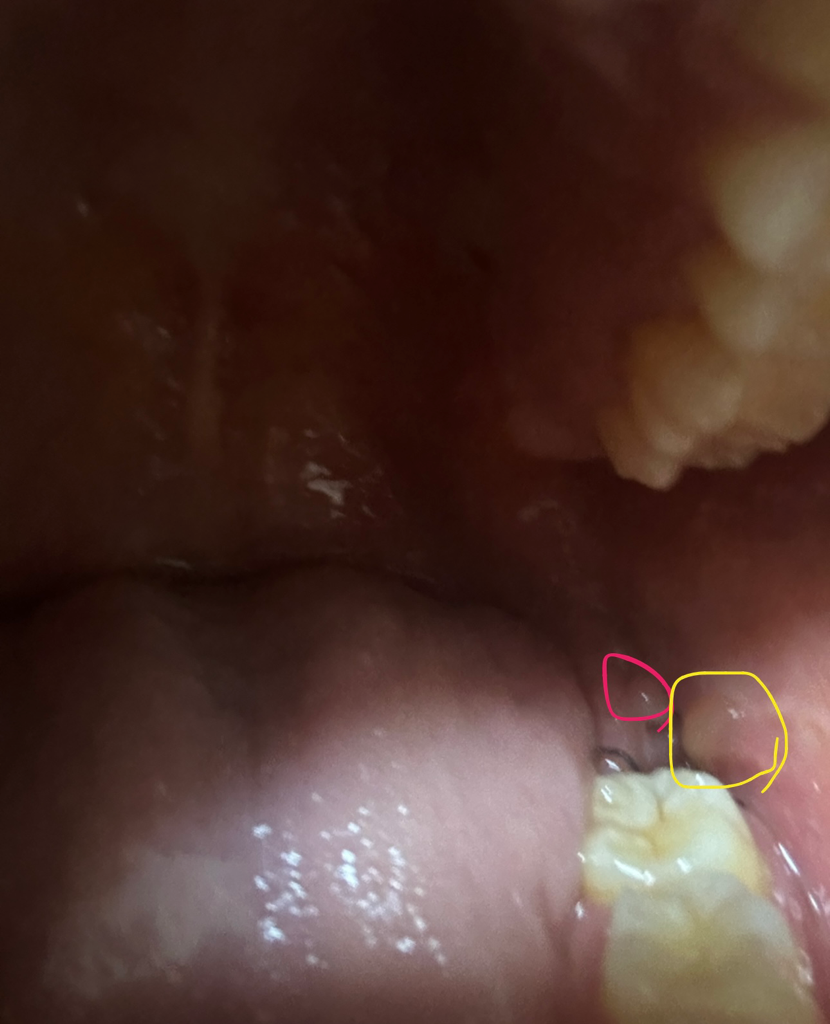

빨간 동그라미는 치과의사선생님께서 치관주위염이라하셨었고 사랑니 발치하기 전부터 원래 있던거에요 지금은 많이 작아졌구요 그런게 발치한지 이틀차인데요 노란색동그라미는 무엇인가요? 염증인가요? 마취풀리고 지금까지 아직 어떠한 통증도없습니다

노란색으로 되어 있는 부분은 볼의 연조직이 발치한 빈 공간으로 들어가서 생긴 것으로 보입니다 크게 문제가 되는 거 같아 보이지 않지만 걱정이 되신다면 치과에서 진료를 받아 보는 것이 좋습니다

염증은 아니고 잇몸이 치유되면서 나타나는 현상입니다. 크게 걱정하지 않으셔도 될것같습니다.

아니오 그냥 단순 술후 붓기입니다.

시술 후 3일간은 붓기가 커지며 회복되는 데에는 최소 일주일이 걸립니다.